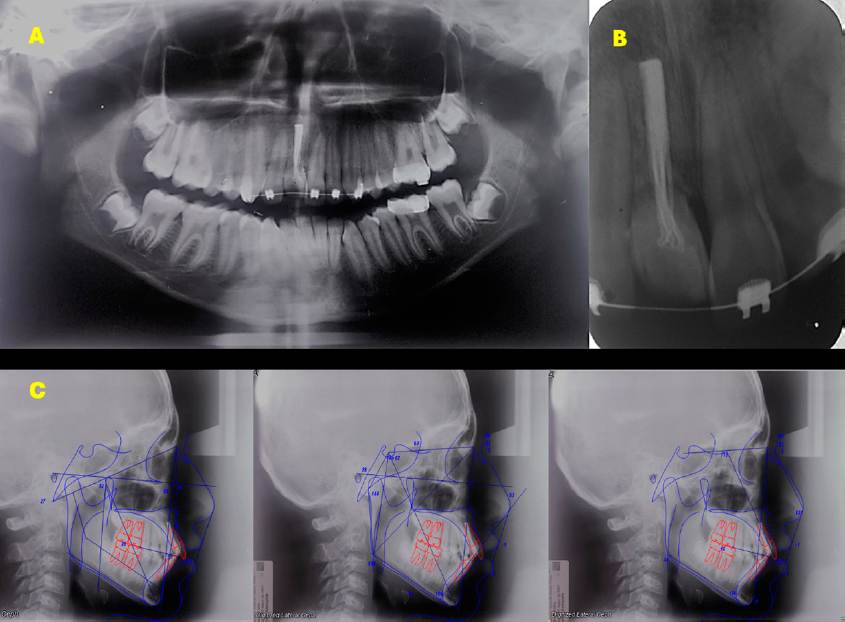

En la ortopantomografía se observó una dentición completa, con presencia del incisivo central superior con reabsorción radicular externa, y material de sellado endodóntico. Este hallazgo se corroboró con la radiografía dentoalveolar. El análisis cefalométrico reveló una relación intermaxilar Clase II (ANB 6°), con la mandíbula en retro posición, leve exceso de la longitud del cuerpo mandibular, inclinación dentoalveolar maxilar. Además, el patrón facial vertical era hiperdivergente (385°) con crecimiento clockwise, y patrón braquifacial. Tenía además palatinizado el incisivo central superior derecho y proinclinación del incisivo central superior izquierdo (Incisivo a plano palatino = 112.6°), y del incisivo central inferior (plano mandibular = 100.1°), aumentando la sobre mordida horizontal y vertical. Juntas, estas características apuntaban a una maloclusión dental que necesitaba corrección por los valores mostrados en la Tabla 1.

Figura 2 Radiografías. A. Ortopantomografía. B. Dentoalveolar del diente 11, donde se observa reabsorción radicular externa y tratamiento de conducto. C. Trazados cefalométricos iniciales.